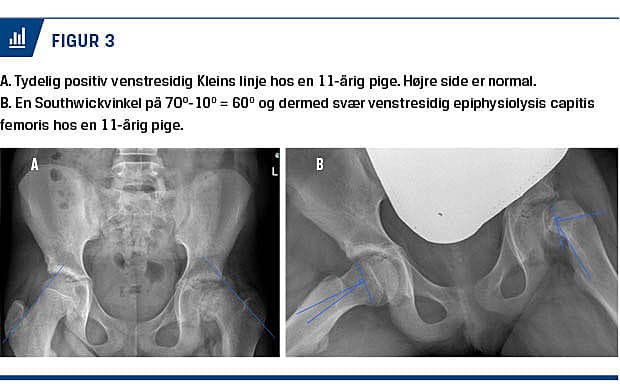

ECF kan diagnosticeres radiologisk ved anterior-posterior (AP)-optagelse af bækken og hofte samt med patienten i frøstilling, den såkaldte Lauensteinprojektion. Lauensteinprojektionen er velegnet til diagnosticeringen, men er ikke standardlateraloptagelsen overlegen [19, 20]. På AP-optagelsen kan diagnosen stilles vha. Kleins linje (Figur 2A og Figur 3A) [14, 21], som dog ved den milde og moderate ECF har lav sensitivitet, hvorfor Lauensteinprojektionen eller lateraloptagelsen altid skal tages [19].

Sværhedsgraden kan bl.a. beskrives ved Southwickvinklen, som måles på Lauensteinprojektionen og

inddeles i mild, moderat og svær. Udmåling af Southwickvinklen fremgår af Figur 2B. Under 30 grader kategoriseres som mild, 30-50 grader karakteriseres som moderat og over 50 grader karakteriseres som svær (Figur 3B). Klassifikationen af sværhedsgraden er af betydning, da mild og moderat ECF har en bedre langtidsprognose end svær ECF [6, 14, 19]. CT er ikke røntgenundersøgelse overlegen i diagnosticeringen [14], mens MR-skanning er mere sensitiv end røntgen og CT, men ikke bruges rutinemæssigt. MR-skanning kan desuden bruges til undersøgelse af vaskulariseringen af epifysen præoperativt og anbefales derfor af nogle som et vigtigt prognostisk værktøj [13, 22].